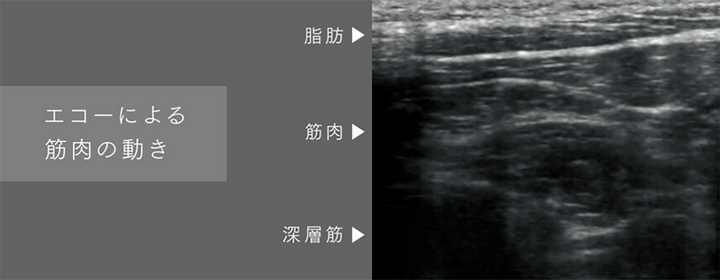

まずは温熱機能で首を効果的に温めて首の緊張をほぐし、EMS機能で筋肉を緩め(※1)、さらに電動牽引機能で、首を押したり引っ張ったりストレッチさせながら自然なカーブへと整えてくれるそう。

EMS機能は「たたき・もみ・つまみ」を再現した3種類のEMSモードと20段階のレベル調整が可能。